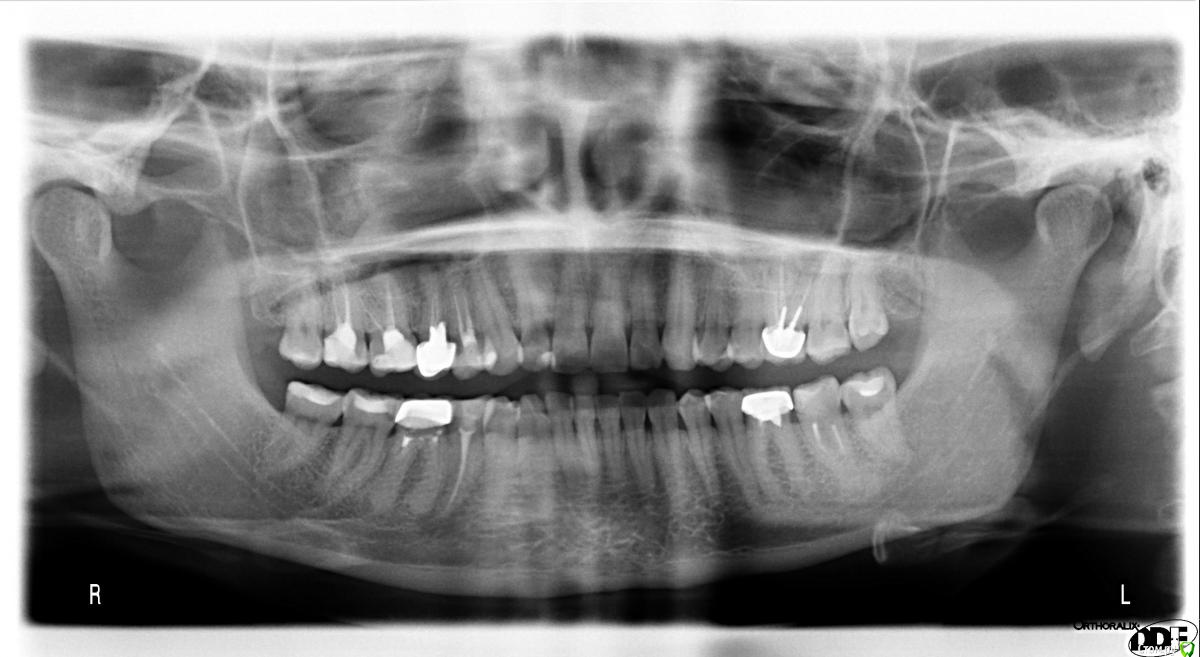

paciente Опубликовано 25 сентября, 2015 Поделиться Опубликовано 25 сентября, 2015 Здравствуйте!Посмотрите, пожалуйста, снимки. Начала болеть десна при нажатии, затем появилась небольшая припухлость щеки снаружи и достаточно сильная внутри, на десне, температура. Сделали КТ, диагноз - киста (зубы верхние справа, если правильно считаю, 4-й и 5-й), которая проросла в гайморову пазуху. Хирург сделал надрез в десне и поставил дренаж, припухлость спала. Прокололи линкомицин в течение недели, плюс прокапала в нос капли полидекса неделю. Есть два мнения хирургов:1. Вырвать два зуба, подождать месяц, сделать повторно КТ и дальше решать с лорами, что делать с пазухой. Подождать четыре месяца и ставить импланты.2. Обратиться в клинику со стационаром, удалить зубы и кисту (удаляет, как я поняла, хирург-стоматолог под контролем лора) зашить (?) образовавшееся отверстие в гайморовой пазухе, подождать десять месяцев и ставить импланты.Оба хирурга считают, что кости будет недостаточно и необходимо будет ее наращивать. Хирург номер два посоветовал для начала обратиться в районную поликлинику. Там хирург мне сходу сказал, что помочь мне не может и что диагноз "киста" невозможно поставить без пункции. На просьбу дать направление туда, где мне могут помочь, попросил принести описание КТ, т.к. он открыть снимок не может, у него нет компьютера. Описание КТ сделать не удалось - в клинике, где я его делала, нет стоматолога, в остальных местах мне отказались делать описание "чужого" КТ. Насколько я понимаю, если делать операцию в рамках ОМС, то это предполагает хождение по мукам из одного заведения в другое, где постоянно будут просить какие-то дополнительные бумажки. Если делать платно - опять же я не совсем понимаю, куда можно обратиться. Звонила в клинику МГМСУ на Вучетича, обхамили еще на попытке записаться, в ЦНИИС за два дня постоянных попыток дозвониться не удалось. Возможно, нужно идти к конкретному врачу, но я не знаю к кому. По состоянию: постоянная температура 37, слабость, прозрачные выделения из правой ноздри, головная боль.На руках диски с КТ и ортопантомограммой. Описания снимков и заключения врачей нет.Выложила принтскрины КТ и оптг. Если нужно, заархивирую КТ и выложу ссылку. Прошу посоветовать, что именно лучше сделать, а также клинику, а лучше врача в Москве. Огромное спасибо за ответ!!! Ссылка на комментарий

AlexanderGudkov Опубликовано 25 сентября, 2015 Поделиться Опубликовано 25 сентября, 2015 Как мне кажется, нужно перелечить зубы 24,25 качественно, хорошо. Ссылка на комментарий

diesel87 Опубликовано 25 сентября, 2015 Поделиться Опубликовано 25 сентября, 2015 Вы выложили скрины шестого зуба, сделайте тоже самое с 4 и 5 зубами. Ссылка на комментарий

Bier Опубликовано 25 сентября, 2015 Поделиться Опубликовано 25 сентября, 2015 тут рядовая ситуация по большому счету. Выложите срезы 4,5 зубов. Ссылка на комментарий

St. Опубликовано 27 сентября, 2015 Поделиться Опубликовано 27 сентября, 2015 1.4, 1.6 перелечивать. 1.5 - сомнительный. можно снять коронку, достать вкладку и оценить оставшийся объем зуба. Если достаточно - пробовать перелечить, если нет - удаление и имплант. Помимо этих зубов обратите внимание на 2.6(верхний слева), 3.6, 3.7(снизу слева) и 4.6 (снизу справа) - в них тоже неидеальное качество лечения каналов. И зубы без нервов с большими пломбами лучше покрыть коронками. Про консервативное лечение у ЛОРа поддерживаю. Ссылка на комментарий

major Опубликовано 28 сентября, 2015 Поделиться Опубликовано 28 сентября, 2015 Извините, конечно речь про 1.4,15,16. Ссылка на комментарий